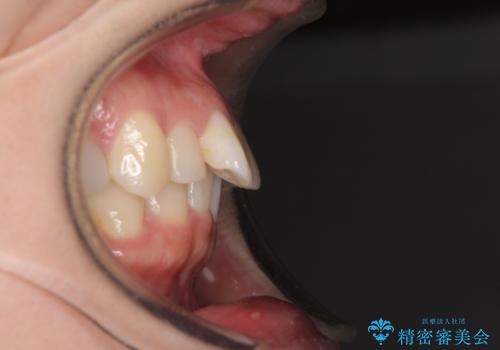

下顎前歯2本が先天欠損しており、上顎歯列に対して、下顎歯列がアンバランスに小さい状況でした。

左右上顎側切歯2本が矮小歯であるため、上顎の抜歯ではなく、IPR(歯と歯の間を削る)と歯列全体の後方移動によってバランスを整えることとしました。

歯列のバランスが悪く、インビザライン矯正特有の奥歯の噛みにくさがなかなか改善されず、治療期間が長期化してしまいました。